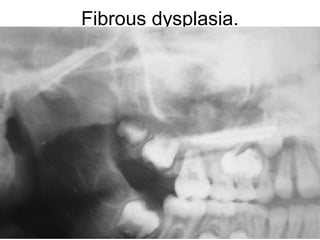

Fibrous dysplasia. Periapical radiograph showing

a diffuse "ground-glass" radiographic appearance.

Fibrous dysplasia.